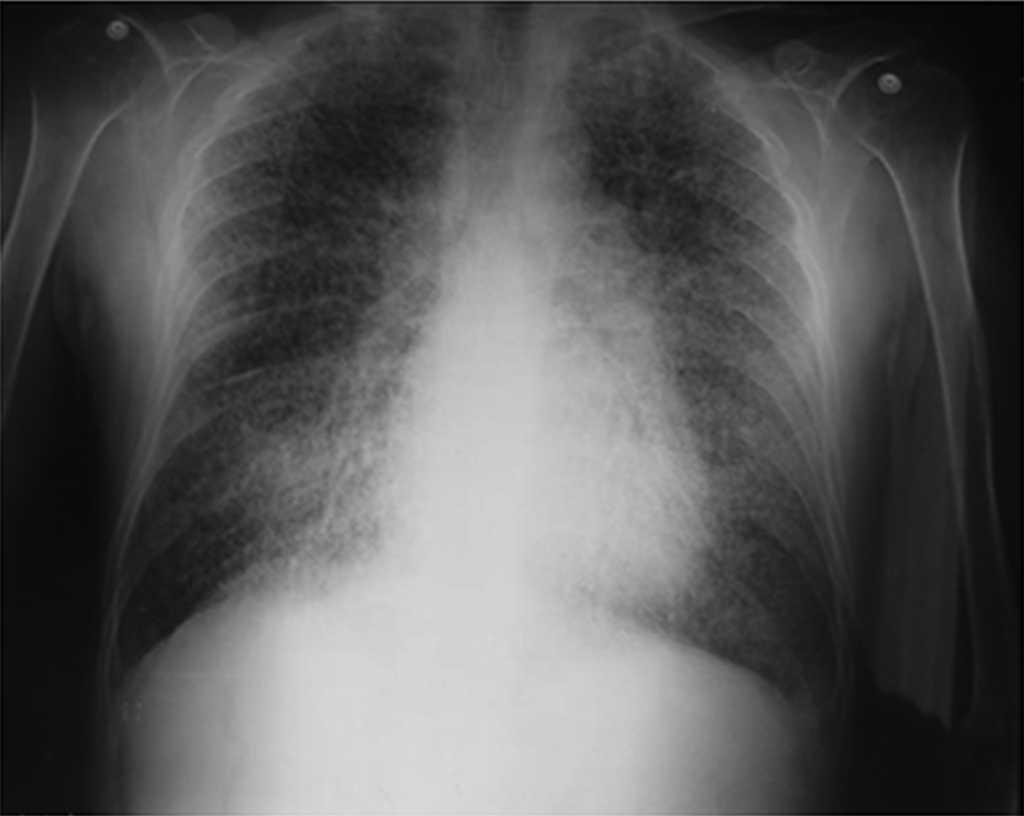

Al ingreso el paciente estaba afebril, deshidratado, con los siguientes signos vitales: presión arterial 120/75mmHg, frecuencia cardiaca 90 latidos por minuto, frecuencia respiratoria 18 respiraciones por minuto. Peso 47,5kg, talla 1,62 metros, índice de masa corporal 18,1 kg/m2. Saturación arterial de oxígeno de 91%, con fracción inspirada de oxígeno de 0,21. Al examen físico general no se encontraron ruidos agregados a la auscultación pulmonar, abdomen blando, sin presentar signos de irritación peritoneal. No se encontró inflamación o dolor articular, manos con deformidades en cuello de cisne y desviación cubital. Sin otras alteraciones llamativas. Electrocardiograma normal. El hemograma mostró anemia con volúmenes corpusculares normales, discreta leucocitosis a expensas de los neutrófilos y ligera trombocitosis. El nitrógeno ureico y la creatinina sérica estaban elevados, parcial de orina con presencia de leucocituria, hematuria, nitritos positivos además de cilindros granulosos. La radiografía de tórax reveló la presencia de opacidades micronodulares difusas en ambos campos pulmonares y en la tomografía de tórax de alta resolución se observaban pequeñas y numerosas calcificaciones del tamaño de «granos de arena».

Dentro de los exámenes diagnósticos se debe realizar, en primer lugar, una radiografía de tórax, que usualmente muestra calcificaciones micronodulares, bilaterales, opacidades reticulares lineales y uniformidad de tamaño de los microlitos distribuidos a lo largo de todo el árbol bronquial. Los anteriores hallazgos se han descrito como «tormenta de arena» (del inglés sandstorm)44 o «tormenta de nieve» (del inglés snowstorm)45, que predominan en las áreas basales y mediales del pulmón, con obliteración de los bordes cardiacos y diafragmáticos35.

Se observan depósitos en las superficies subpleurales, resultando en una opacidad lineal, que demarca las divisiones pulmonares y mediastinales46, conocida como línea negra pleural (del inglés black pleural line), la cual fue descrita por Felson, considerada como una ilusión visual secundaria a un área radiolucente que se da entre el parénquima pleural y las costillas45,47–50. Otros hallazgos típicos son pequeñas bulas apicales e imagen en panal de abejas, sin mención de compromiso de nódulos linfáticos51.

En aquellos casos en que existe el antecedente familiar de MAP, el diagnóstico se establece con el cuadro clínico y los hallazgos imagenológicos ya sea radiografía o tomografía de tórax con infiltrados pulmonares con patrón en tormenta de arena, calcificaciones micronodulares a lo largo de los paquetes broncovasculares, engrosamiento de los septos interlobulares, que comprometen de manera predominante y simétrica a los lóbulos inferiores, sin necesidad de someter al paciente a pruebas invasivas como fibrobroncoscopia y lavado broncoalveolar.

El presente caso reportado hace referencia a un caso de MAP, diagnosticada mediante imágenes diagnósticas y estudios anatomopatológicos, que fueron revisados por varios especialistas en las áreas de neumología y patología de la ciudad de Bogotá.